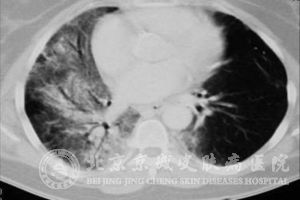

2.放疗一个月后的急性期可在受照射的肺野出现大片密集的片状模糊阴影及少数网状阴影。慢性期肺部呈纤维化,在肺门、纵膈两侧及其他受放射的肺野有网状、条索状或团状的收缩阴影。

3.因肺纤维的收缩会导致气管和心脏向患侧移动,太高了同侧的横膈,出现正常肺组织的代偿性肺气肿。

4.当发生肺动脉高压时,出现肺动脉段突出或者右心的肥大;常有胸腔积液。

5.肺部受损伤的部位应与受照射的部位一致,一段时间后可发现在纤维化后的病灶会回缩,但是转移癌却在增大。